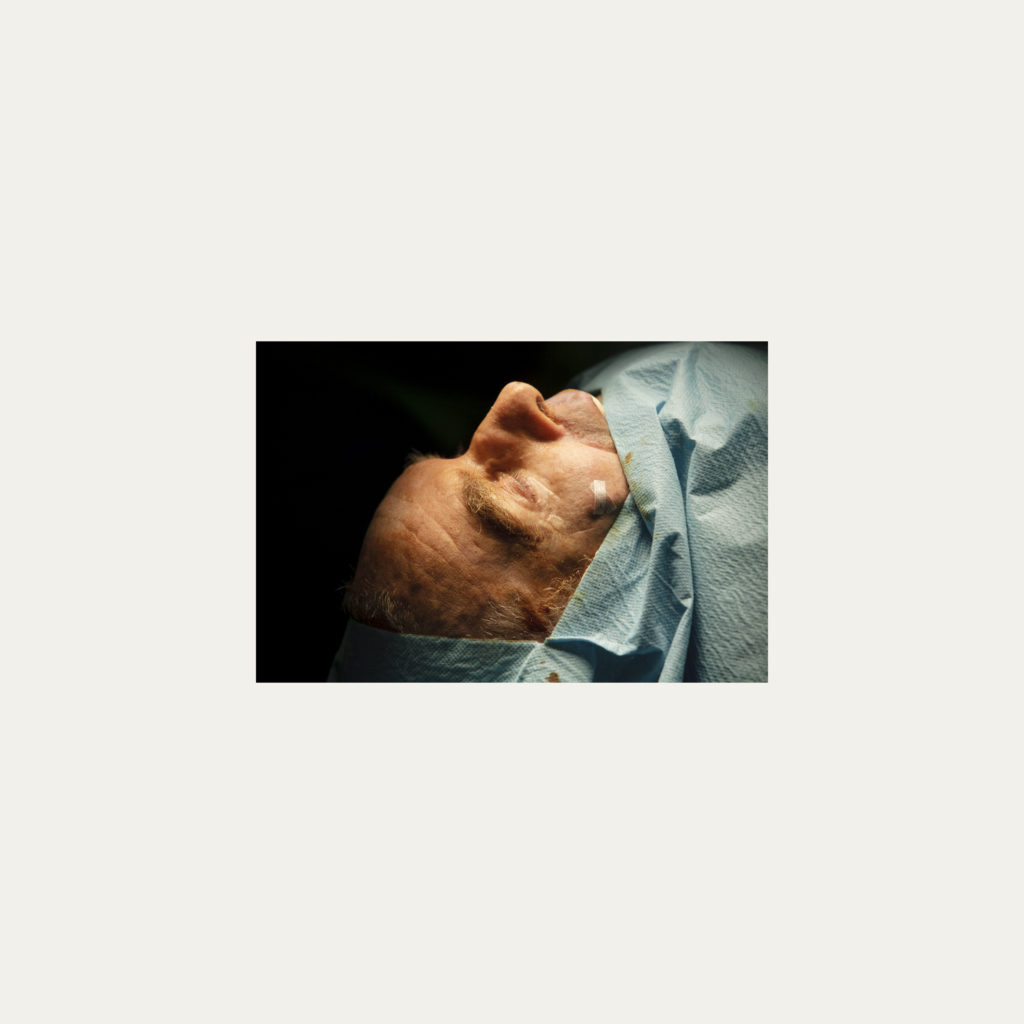

« Nature Morte » est la recherche de l’instant, pendant une intervention chirurgicale où la tête du patient opéré se retrouve seule dans le champ photographié. Aucune main intervenant, peu d’instruments chirurgicaux visibles, laissent le fragment de corps opéré existé pour lui-même. Les têtes, ainsi isolées, en deviennent presque des objets.

Cette approche est intensifiée par la présentation : dans de grands cadres carrés et passe-partout blancs, les photos de petit format font référence aux papillons épinglés de la collection d’un entomologiste.

Face à ces images, une forme de recueillement est nécessaire, s’approcher doucement pour s’approprier tous les détails des images.

Le caractère éminemment esthétique est souligné/donné par les gammes de couleur, la lumière précise sur la tête photographiée, les brillances partielles, renforçant également l’aspect pictural, les textures réelles.

L’humain présent dans ces images est celui qui rompt avec l’invisible et donne à voir l’architecture même de sa chair.